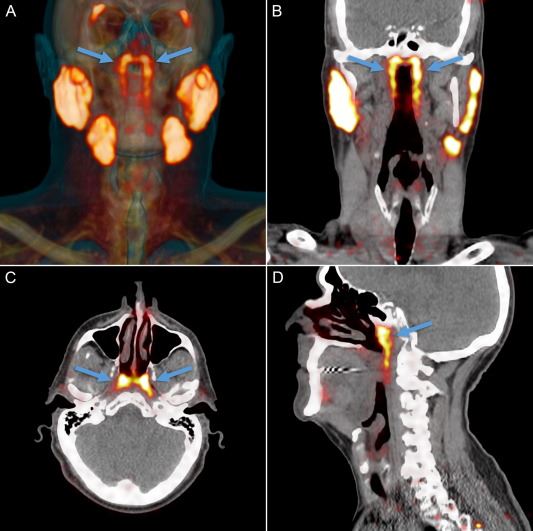

Segalanya bermula selepas saintis yang mengkaji kanser prostat menjalankan satu siri imbasan CT dan PET ke atas pesakit yang disuntik glukosa radioaktif yang menjadikan tumor bersinar pada imbasan.

Pasukan di Institut Kanser Belanda menyedari bahawa dua kawasan di dalam kepala pesakit menyala dan mendapati bahawa satu set kelenjar air liur tersimpan di sana.

Dari situ, barulah mereka sedar akan satu organ baharu yang disebut sebagai tiub kelenjar air liur.

Fungsi tiub kelenjar ini adalah untuk memastikan kawasan tekak di belakang hidung serta mulut dalam keadaan basah dan tidak kering.